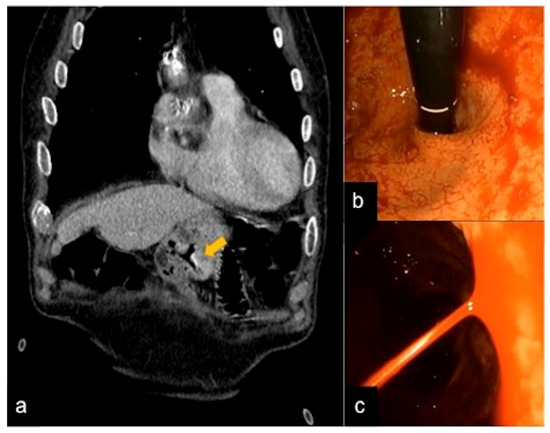

| Diverticulosis (Figure 33) | Asymptomatic or bleeding. | Protruding sacs where the vessels pass through the muscularis layer, between the mesenteric and antimesenteric taenia. |

| Angiodysplasia (Figure 5 and Figure 34) | Asymptomatic or bleeding. | Small hyperdense nodules within the intestinal wall, best defined in the portal phase of the study. |